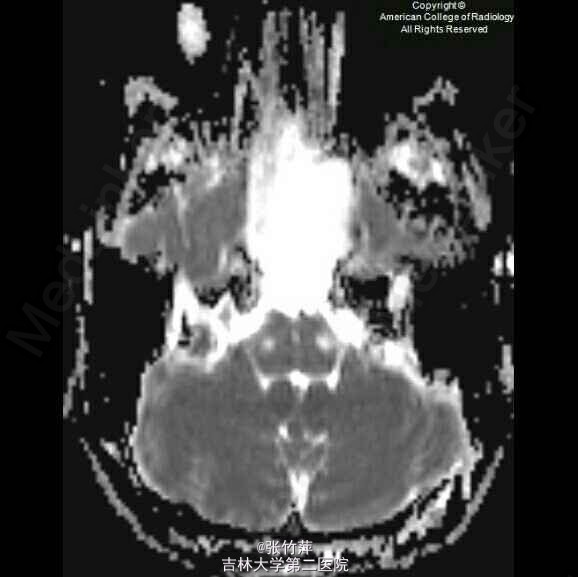

女,20岁。头痛一月余,伴复视,流泪,视力下降。

脑部磁共振图片如下

蝶窦粘液囊肿